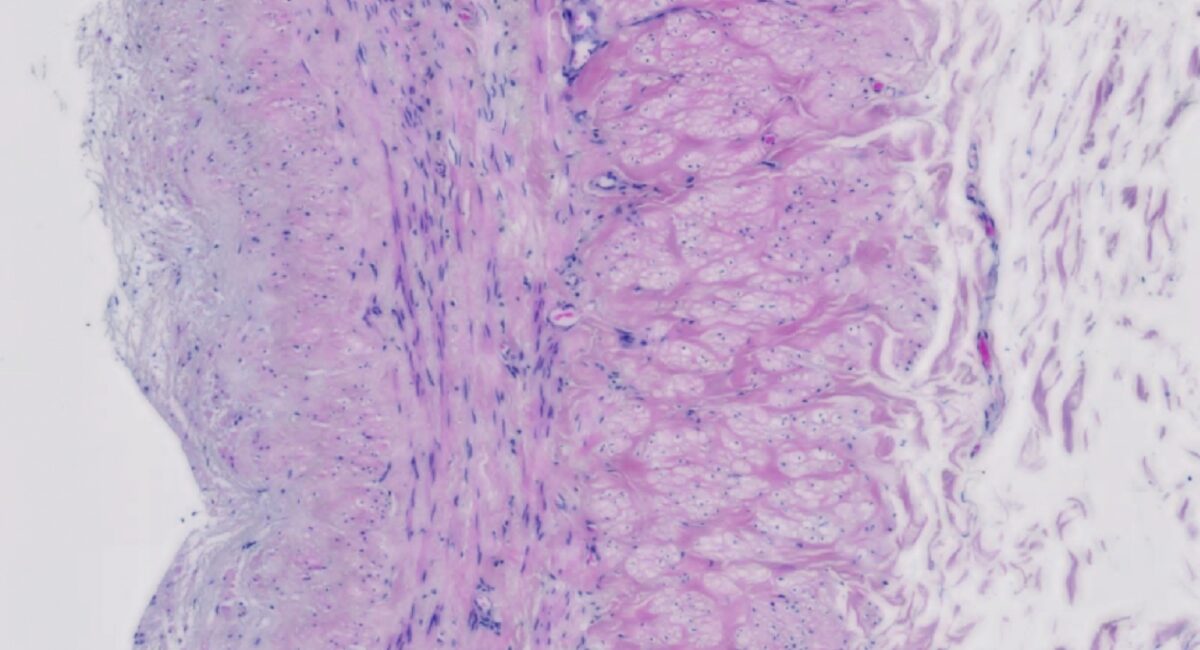

Vein grafts are required in patients with multi-vessel coronary artery disease. For example, in coronary artery bypass graft (CABG) surgery, venous tissue taken from the patient’s leg is used to bypass the blocked region. Over time these grafts can narrow and eventually fail, partly due to damage to the vessel wall caused during surgery. Vascular smooth muscle cells are a predominant constituent of the blood vessel wall, and after undergoing damage, can become hyper-proliferative. This hyper-proliferation of smooth muscle cells in the graft causes narrowing of the luminal space, leading to neointima formation and eventual graft failure. Vein graft failure affects around 30-50% of patients within ten years of surgery, resulting in a need for further treatment, and significant additional costs to healthcare providers. Targeting, and limiting smooth muscle cell proliferation is considered a promising therapeutic target to prevent vein graft failure.

Edinburgh researchers have identified and characterised a long non-coding ribonucleic acid (RNA), called SMILR, which is up-regulated in proliferating vascular smooth muscle cells and plays a key role in regulating their proliferation. SMILR is present in the plasma of cardiovascular disease patients and found at increased levels in unstable regions of atherosclerotic plaques. Therapeutic targeting of SMILR could be a means to inhibit vascular remodelling and reduce or prevent vascular diseases. It is a very attractive target for anti-proliferative approaches with potential applications as a biomarker for detecting unstable atherosclerotic plaques, and it is also amenable to Ribonucleic acid interference, small molecule or gene therapy approaches.